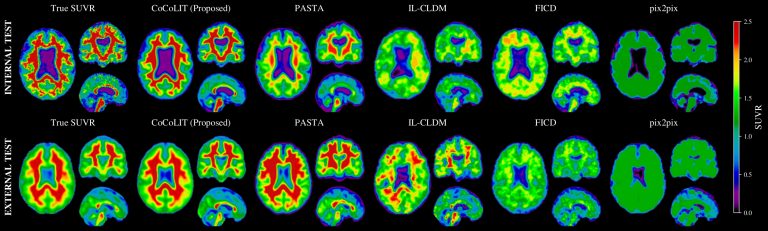

Il progetto CoCoLIT rappresenta una svolta nell’ambito della diagnostica precoce dell’Alzheimer:...